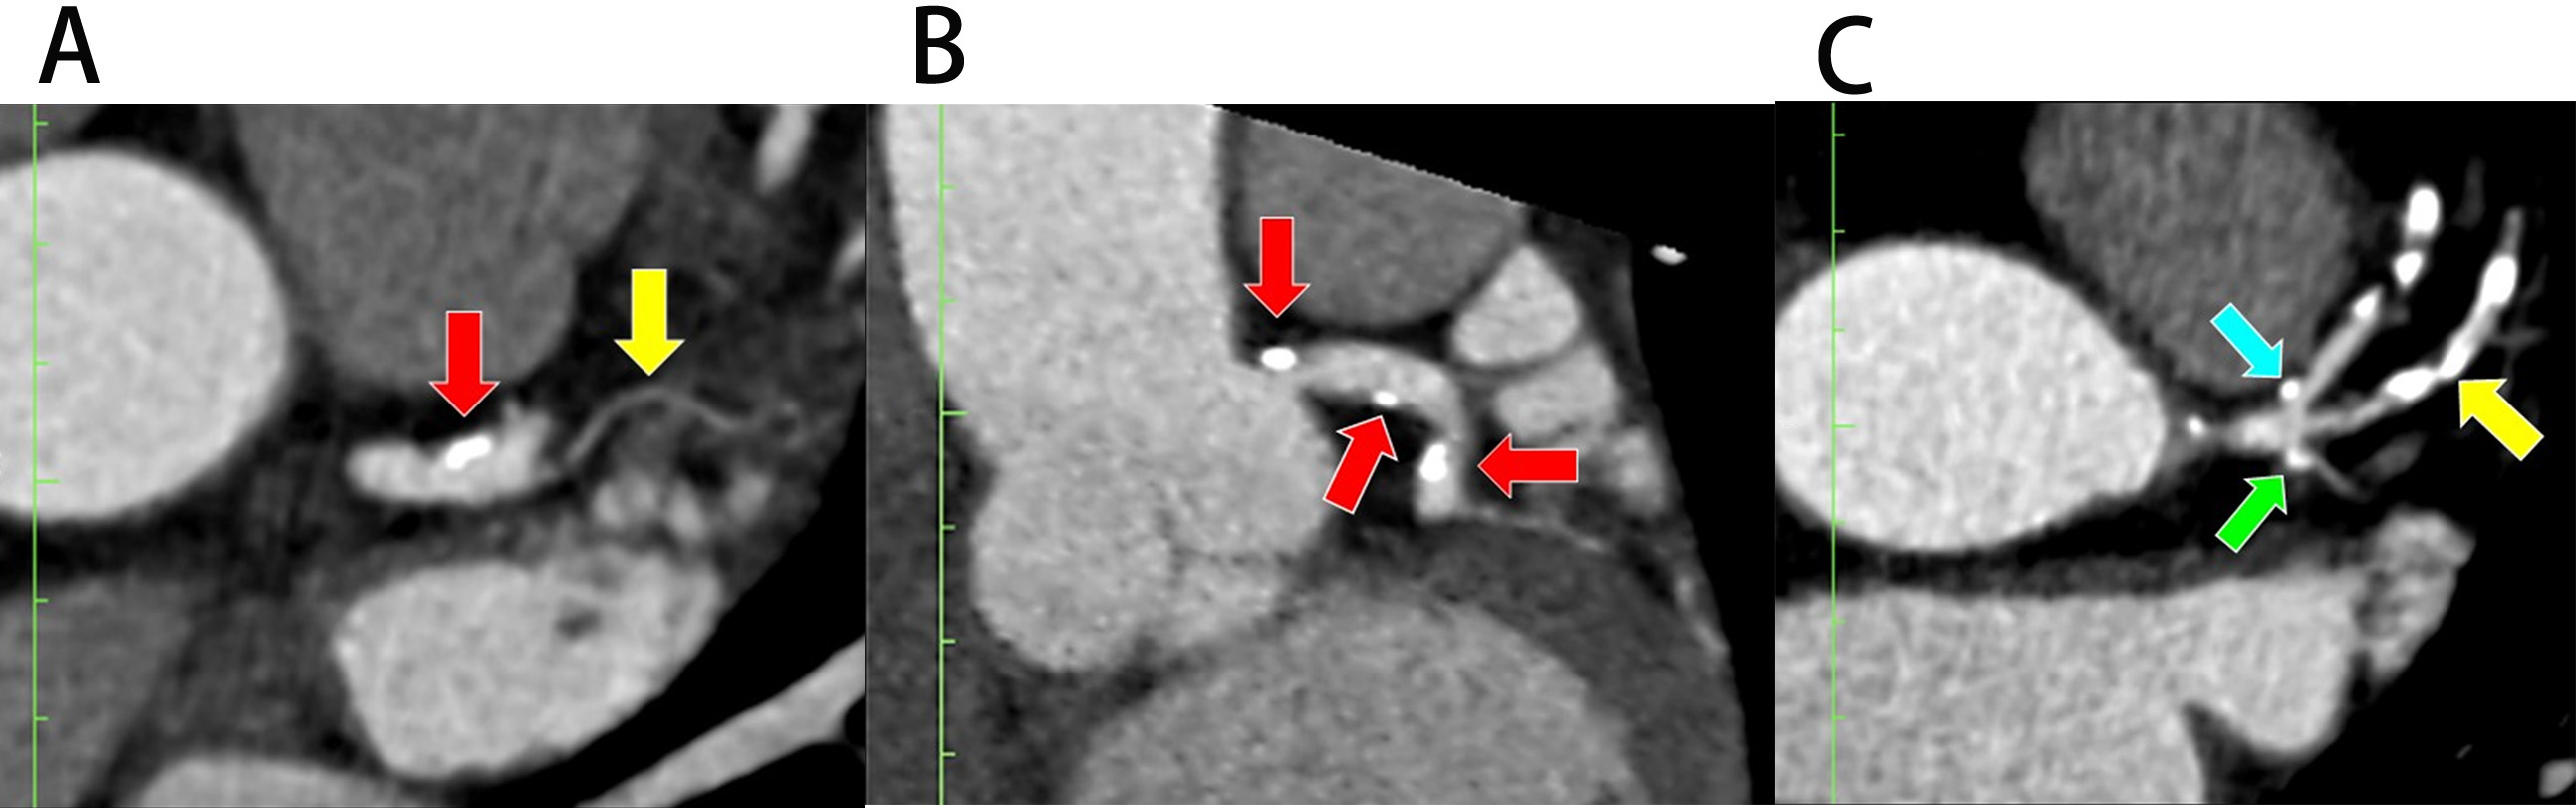

Analysis of the LBR in this study was made according to the techniques described by Beton et al. (2017) [21]. Briefly, identification of the plaque location in the LMCA, proximal left anterior descending (pLAD), and proximal left circumflex (pLCx) were made at a specific distance as illustrated in the schematic diagrams (Fig. 2A, Fig. 3A, and Fig. 4A). The LMCA was taken as the parent vessel, whereas the pLAD and pLCx arteries were considered as the daughter vessels. The analysis was made within a 10 mm distance from the distal end of the LMCA and within a 10 mm distance from the ostia of the daughter vessels [21]. Images were reconstructed in a multiplanar reconstruction (MPR) format and analysed using the Centricity Picture Archiving and Communication System, Universal Viewer Version 5.0 (GE Healthcare, Chicago, IL, USA) (Fig. 2B–D, Fig. 3B, and Fig. 4B). A consistent setting was used to analyse the presence of the RI and LBR [20]. Those patients with the presence of RI were categorised into the “Experimental” group, and their data were analysed against patients with the absence of RI were categorised into the “Control” group (Fig. 1).

Fig. 2. The demarcation and identification of the left main coronary artery (LMCA) in a schematic diagram and in multiplanar reconstruction (MPR) images. (A) Schematic diagram of proximal and distal portions of LMCA. (B) Proximal and distal portions of LMCA in MPR (axial view). (C) Left bifurcation region in MPR (axial view). (D) The LMCA in the MPR (coronal view). Yellow dots indicate the marking for the ostia of the daughter arteries, “a” indicates the proximal portion of LMCA, “b” indicates the distal portion of LMCA (red line), the blue line indicates 10 mm from pLAD ostium, and the green line indicates 10 mm from pLCx ostium. Ao, aorta; pLAD, proximal left anterior descending artery; pLCx, proximal left circumflex artery.

The LBR analysis investigated the association between the RI and atheroma formation near the LBR, with particular attention paid towards any predilection for the medial or lateral walls of the daughter arteries. In this study, the LMCA was divided into proximal (labelled “a”) and distal (labelled “b”) portions (Fig. 2A,B). The distal portion is defined as the area within a 10 mm distance from its distal-most ostium (depicted as the area between the red to yellow dotted lines, Fig. 2A). In the MPR images, the actual measurement of the distal portion of the LMCA taken at axial and coronal views are demonstrated in Fig. 2B–D.

Plaque analyses in the pLCx and pLAD arteries were made within a 10 mm distance from their ostia (i.e., the pLAD ostium was marked with a blue dotted line and the pLCx ostium was marked with a green dotted line, Fig. 3A and Fig. 4A). The actual measurement that was taken using MPR images is shown in Fig. 2C. To investigate the preference of plaque formation in either walls of the daughter vessels, the pLCx and pLAD were further subdivided into medial (labelled “d” for pLAD and “f” for pLCx) and lateral (labelled “c” for pLAD and “e” for pLCx) walls (Fig. 3A,B, Fig. 4A,B). A plaque was identified as a hyperdense region within the arterial wall that can either show a calcified, non-calcified, or mixed appearance. The presence of atheroma in the LMCA, pLAD and pLCx were documented.